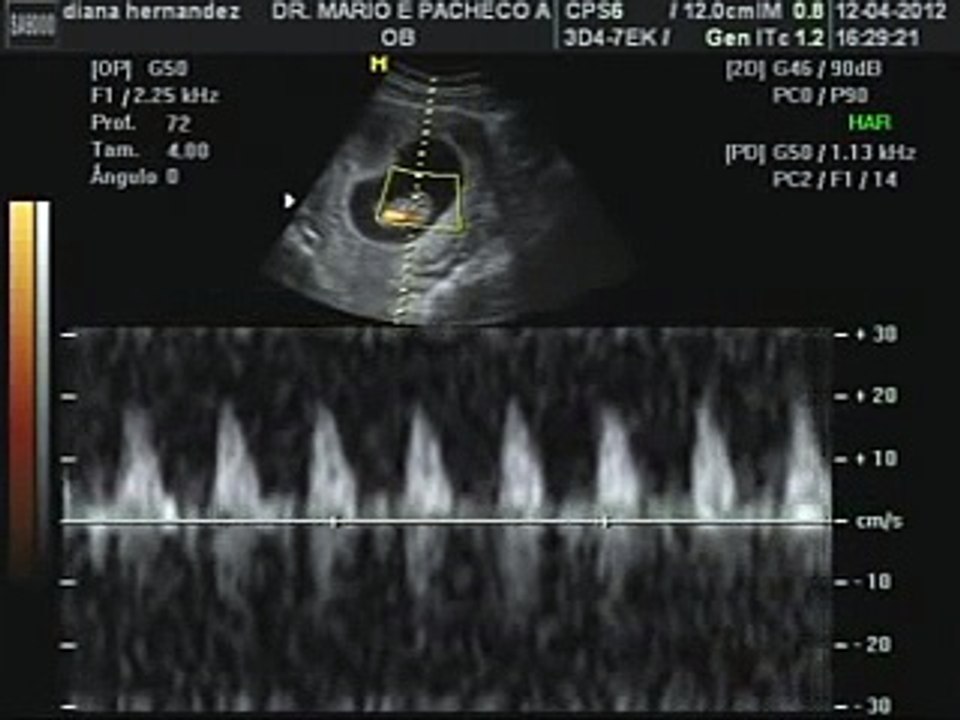

Ultrasonido bebe de 7 semanas de gestacion

¡Ya estás en la semana 7 de embarazo!El riesgo de pérdida reproductiva a las seis y siete semanas de gestación aumenta 19 veces cuando la frecuencia cardíaca embrionaria es menor de 90 lpm (RR 199, IC 15,525,6) y siete veces cuando esta entre 90 y 100 lpm (RR 7,1, IC 4,112,5) Figura 1 Frecuencia cardiaca embrionaria/fetal de acuerdo a la longitud cefalo nalgas del embrión Mis fechas no coinciden con las del ginecólogo Un embarazo normal tiene una duración de entre 37 y 40 semanas, aunque puede prolongarse dos semanas más Esta duración se estima desde la fecha de última regla (o FUR) que es un hecho fácil de detectarse por la mujer y que se ha utilizado desde siempre para el cálculo de la edad gestacional

Se estima que aproximadamente a las cinco o seis semanas de gestación, el corazón del bebé comienza a latir Justo en esos momentos, la frecuencia cardíaca del feto es de 80 a 85 latidos por minuto, considerándose así absolutamente normal Justo a partir de este momento, la frecuencia cardíaca aumentará su ritmo en alrededor de tres latidos por minuto por día, a lo largoBebé de 8 semanas de embarazo Última actualización 29 de abril de 17 a las 2113 por CCM Salud En la octava semana de embarazo, el bebé tiene seis semanas de vida Mide alrededor de 2 cm y sus pulmones, riñones, intestino e hígado ya están formados La futura mamá sufre cambios bruscos de humor, fatiga y náuseas En respuesta a elis_ Hola, la semana pasada cumplí 7 semanas de embarazo y tuve mi primera cita en el ultrasonido no se vio el latido cardiaco del bebé la doctora me dijo que podían hacerme el legrado o podía esperar a ver si el aborto se daba en forma natural Yo siento que mi bebé está bien es un fuerte sentimiento